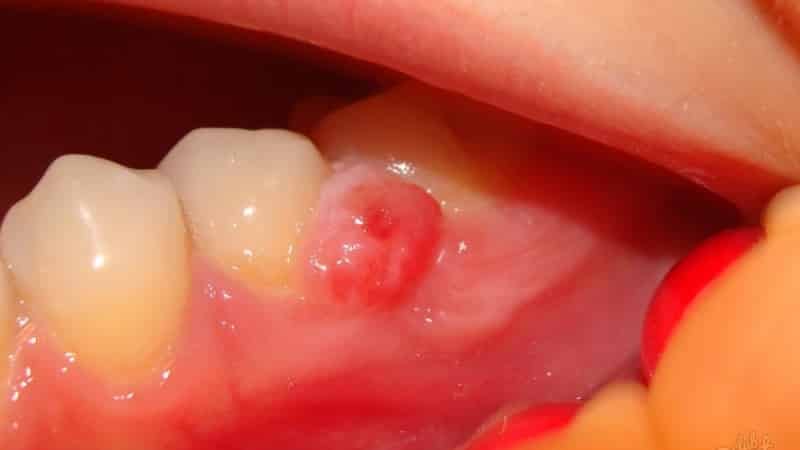

Большинство из этих образований могут долгое время оставаться незамеченными и безболезненными. Однако, достигнув определенных размеров, они могут проявляться в виде выпуклого округлого образования с истончением стенки челюсти.

Симптоматика зависит от характера воспалительного процесса. При хронической форме наблюдаются дискомфортные ощущения в зубе, особенно при употреблении твердой пищи. В некоторых случаях может происходить смещение зубов и их потемнение. Рост кисты усиливается, когда организм ослаблен в борьбе с инфекцией, что приводит к воспалению с образованием гнойных масс. В результате зуб начинает болеть, появляется выраженная отечность и свищи. У пациентов могут возникать головные боли, общее недомогание, слабость, повышенная температура и увеличение лимфатических узлов. В таких случаях крайне важно незамедлительно обратиться к специалистам.

Если после выполнения процедур киста в челюсти продолжает расти, применяется апикальный хирургический метод лечения.

В ходе этой операции хирург удаляет содержимое кистозного образования, а затем извлекает корневую часть зуба, которая была поражена инфекцией. После этого производится пломбирование изнутри, и разрез сшивается. В случаях, когда, например, киста зубов нижней или верхней челюсти возникает повторно, может потребоваться удаление зуба с последующей установкой имплантата. Современные стоматологические технологии предлагают различные решения проблемы, позволяя сохранить зуб при возможности.